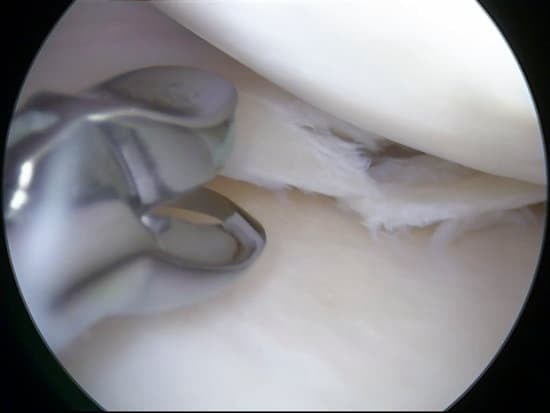

무릎 관절경 수술: 절차와 회복 가이드

무릎 관절경 수술: 절차와 회복 가이드무릎 관절경 수술은 작은 절개를 통해 관절 내부를 검사하고 치료하는 최소 침습 수술입니다.주로 연골 손상, 반월상 연골 파열, 인대 손상, 또는 관절염